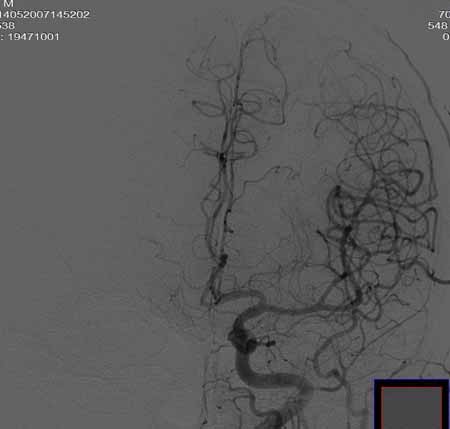

男,60岁。

腹主动脉、颈总动脉、颈内动脉狭窄支架置入术,最少放了三个支架吧,得十几万吧。

颈总动脉支架置入术。